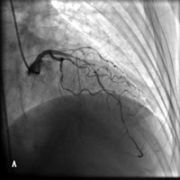

- 超声心动图正常心脏声像图先天性心脏病超声诊断心脏瓣膜病超声诊断心肌病超声诊断冠心病、心脏肿瘤、心包疾病超声诊断内容概述先天性心脏病心脏瓣膜病心肌病冠状动脉粥样硬化性心脏病心脏肿瘤和血栓心包疾病禁忌症适应症概述探头频率成人儿童检查前准备无需特